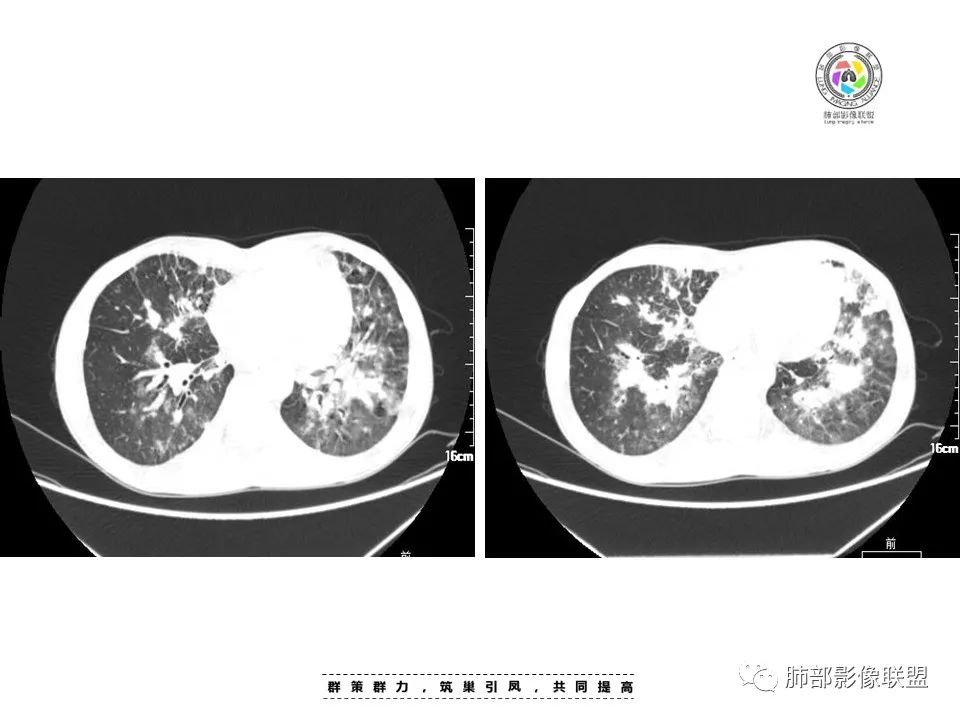

周一晚读病例:男性45岁,发热、纳差,全身散在暗紫色皮疹,结合CD4,符合HIV;肺部影像表现:两肺散在实性结节及磨玻璃密度影,实性结节伴晕征,部分沿支气管血管束分布,支气管血管束增粗,以两肺下叶为著,类似火焰征,双侧胸腔少量积液;首先考虑卡波西肉瘤,鉴别淋巴瘤增值性病变,淋巴瘤样肉芽肿/淋巴瘤,最后挂上马尔尼菲青霉菌病。

两肺弥漫性性结节状、小片状及片状带晕的病灶,煎蛋征、点晕征,主要分布两肺中下叶,病灶周围小叶间隔增厚呈网格状影,部分病灶累及胸膜,伴两侧胸膜增厚。

2.本例双肺小叶间隔增厚明显,多发结节影及片状实性密度影,沿血管支气管束分布为主,两侧较为对称,病灶多环以磨玻璃晕,边界不清。

双侧胸腔少量积液。双肺门及纵隔未见明确肿大淋巴结,纵隔结构间隙模糊。

3.有学者将这种具有沿双肺支气管束分布的实性密度片影描述为“火焰征”,认为具有一定特征性,单就影像表现而言,这种影像表现也可以见于其他病损或多种病理改变的叠加。

1.结节型:两肺沿支气管血管束分布的结节影,呈火焰状或星芒状、挂果征,局部周围出血磨玻璃影(肺泡出血或水肿)。

2.支气管血管束增粗型:

肺门周围支气管壁呈“套袖样”改变。

3.肺炎渗出型:

斑片渗出影,部分融合呈“火焰样”,同时有火焰样结节,小叶间隔增厚等表现。

还可以有纵隔及腋下淋巴结增大,胸腔积液等表现。